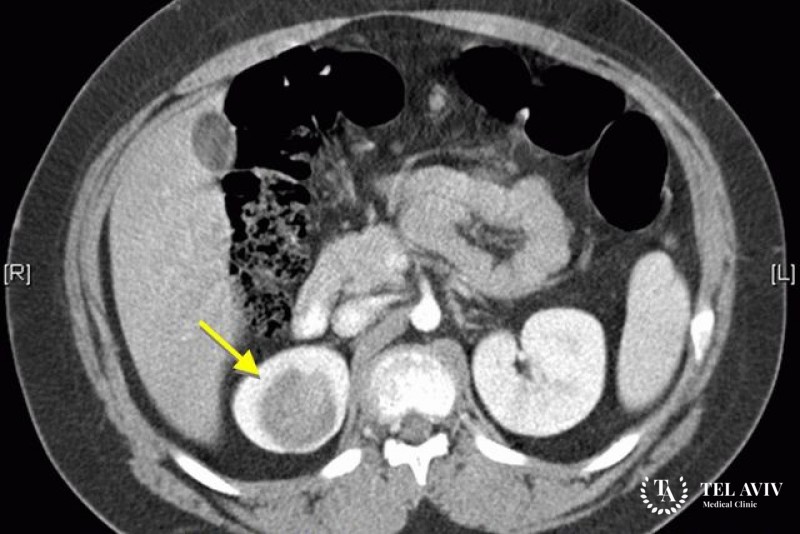

- Компьютерная томография.